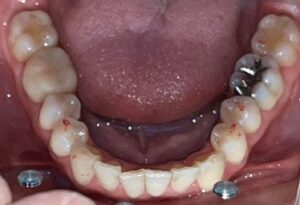

本日は、ジルコニアセラミック(歯科用人工ダイヤモンド)を使用した

メタルフリー治療の症例をご紹介いたします。

治療前は、メタルの詰め物が多数入っておりましたが、

患者様より詰め物を白くキレイにしたいとのことで治療を行いました。

Before After

メタルフリーになり、お口の印象がとても明るくなりました!

メタルフリー治療を行うと、審美的な改善が大きいですが

それだけではありません!

詰め物、被せ物にジルコニアセラミックを使用することで

経年的な摩耗や変色を最小限に抑える、

金属アレルギーのリスクがない、

歯質との適合性が高く、むし歯の再発リスクが低いなど、様々なメリットがあります。

前歯のレイヤリングジルコニアは特に色味や形態をぴったり合わせるため、

セラミストが写真撮影、デジタルトライインを行って作成します。

笑顔がさらに素敵になりましたね✨

患者様にも、とても喜んでいただけました😊